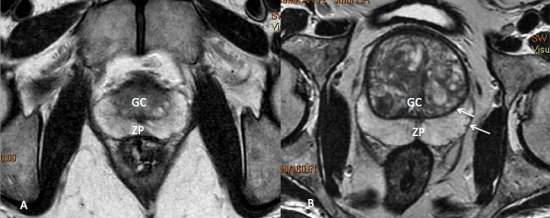

No estadiamento locorregional do câncer de próstata, o aspecto mais relevante na tomada de decisão terapêutica é a diferenciação entre tumor confinado ao órgão (T1 e T2) e tumor localmente avançado, sob as formas de extensão extracapsular (T3a) ou invasão de vesículas seminais (T3b). Para esta avaliação, as imagens ponderadas em T2 são as mais indicadas15,18(fig. 5 e 6).

Figura 5. Estadiamento de adenocarcinoma de próstata Gleason 7. Imagem ponderada em T2 evidencia nódulo no terço médio da zona periférica direita, notando-se pequena irregularidade da cápsula prostática adjacente à lesão, sugestivo de extensão extra-capsular.

Figura 6. Estadiamento de adenocarcinoma da próstata Gleason 9. A) Lesão hipointensa comprometendo quase toda a glândula, com extensão para a gordura periprostática à direita. B) Comprometimento das vesículas seminais.

Os critérios de imagem para extensão extracapsular incluem assimetria ou envolvimento macroscópico dos feixes neurovasculares, abaulamento focal do contorno prostático, espiculação ou irregularidade do contorno prostático, obliteração do ângulo retoprostático, retração capsular, e sinais de rotura capsular com extensão direta a gordura periprostática. Lesões que exibem contato maior que 1,0 cm com a cápsula prostática apresentam maior risco de extensão extracapsular.15,18

Os achados que indicam invasão das vesículas seminais incluem: aumento de tamanho, assimetria e hipointensidade das vesículas seminais, obliteração do ângulo vesicoprostático e extensão direta da base prostática à vesícula seminal, sendo este achado o de maior valor preditivo positivo.15,18